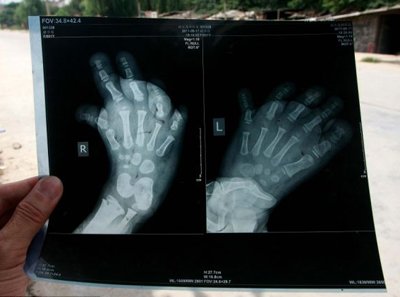

Маленькой китаянке Ю Ю проживающей в городе Ксиан, местные врачи не могут поставить точный диагноз. Об этгом пишет Day.az.

Ноги Ю Ю развились настолько неправильно, что она практически не может передвигаться без посторонней помощи.